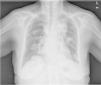

Presentamos el caso de una mujer de 70años, con antecedentes de diabetes mellitus tipo2, dislipidemia y síndrome depresivo. Alérgica al ibuprofeno. Sin hábitos tóxicos ni exposiciones ocupacionales. Trabajaba como ama de casa. Sin antecedentes familiares de interés. Colecistectomizada hace 30años. Tratamiento habitual con metformina, atorvastatina y escitalopram. Acude al servicio de urgencias por cuadro de 2meses de evolución consistente en tos seca, pérdida de peso de 10kg, astenia y anorexia, dolor en la región lumbar derecha y hematuria intermitente en el último mes. Examen físico dentro de la normalidad. Las pruebas de laboratorio revelaron una bioquímica con aumento de fosfatasa alcalina (225UI/l) y gammaglutamiltransferasa (GGT) de 119UI/l. En el hemograma destacaba una hemoglobina de 8g/dl. La radiografía de tórax mostró una masa en el lóbulo superior izquierdo y múltiples nódulos bilaterales. Se realizó tomografía axial computarizada de tórax, abdomen y pelvis, evidenciándose en tórax una opacidad nodular en lóbulo superior izquierdo de unos 45×35mm, múltiples nódulos subpleurales bilaterales, adenopatías torácicas en distintas localizaciones y pequeño derrame pleural bibasal. A nivel abdominopélvico se objetivó una gran masa renal izquierda, lesión lítica en hemicuerpo vertebral derecho y nódulo de 15mm en glándula suprarrenal izquierda. Se realizó fibrobroncoscopia, evidenciándose signos de infiltración neoplásica submucosa en bronquio para lóbulo superior izquierdo. La biopsia bronquial y el broncoaspirado citológico fueron negativos para células neoplásicas. Posteriormente se llevó a cabo punción-aspiración con aguja fina de la masa de lóbulo superior izquierdo, llegándose al diagnóstico anatomopatológico de metástasis pulmonar de sarcoma renal de células claras de tipo epitelioide.

El sarcoma renal de células claras es una neoplasia poco frecuente y de histogénesis desconocida. Se suele presentar en la edad pediátrica, entre los 1 y 3años de edad, son muy raros antes de los 6meses y no se describen casos en adultos1. Las manifestaciones clínicas del sarcoma renal de células claras son fundamentalmente de 3tipos: urológicas, generales y producidas por síndromes paraneoplásicos2. Entre las manifestaciones generales destacan astenia, anorexia, pérdida de peso (síntomas presentes en nuestro caso), febrícula, síntomas gastrointestinales como náuseas, vómitos, estreñimiento y dolor abdominal, siendo estas manifestaciones inespecíficas y comunes a otras neoplasias renales3. Entre los síntomas paraneoplásicos predominan la anemia y el síndrome de Stauffer, definido este último como la alteración en las pruebas hepáticas de causa no metastásica, en especial las relacionadas con la presencia de colestasis (GGT y FA). Ambos hallazgos, anemia y síndrome de Stauffer, fueron hallados en nuestra paciente. El sarcoma de células renales se disemina por extensión directa linfática y a distancia por vía hematógena o linfohematógena4. Las localizaciones y la frecuencia de invasión son pulmón, ganglios linfáticos, hueso, hígado, riñón contralateral, suprarrenales y cerebro. Las metástasis pulmonares aparecen generalmente como nódulos múltiples, aunque también se han observado nódulos solitarios. Las metástasis óseas son líticas, rara vez blásticas. Sus localizaciones preferentes por orden de frecuencia son costales, vertebrales, hueso iliaco, fémur, húmero y cráneo5 (fig. 1).